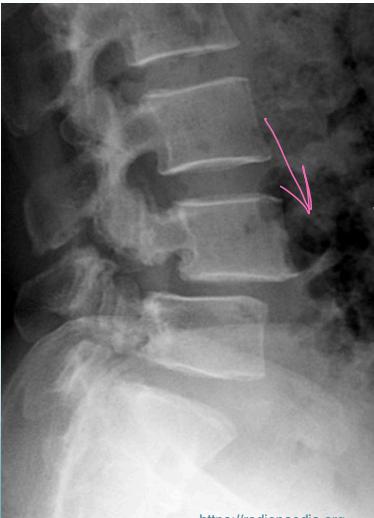

Diagnostic Imaging

- Lateral view: Shows vertebral slip

- Oblique view: Shows decapitated Scottie dog